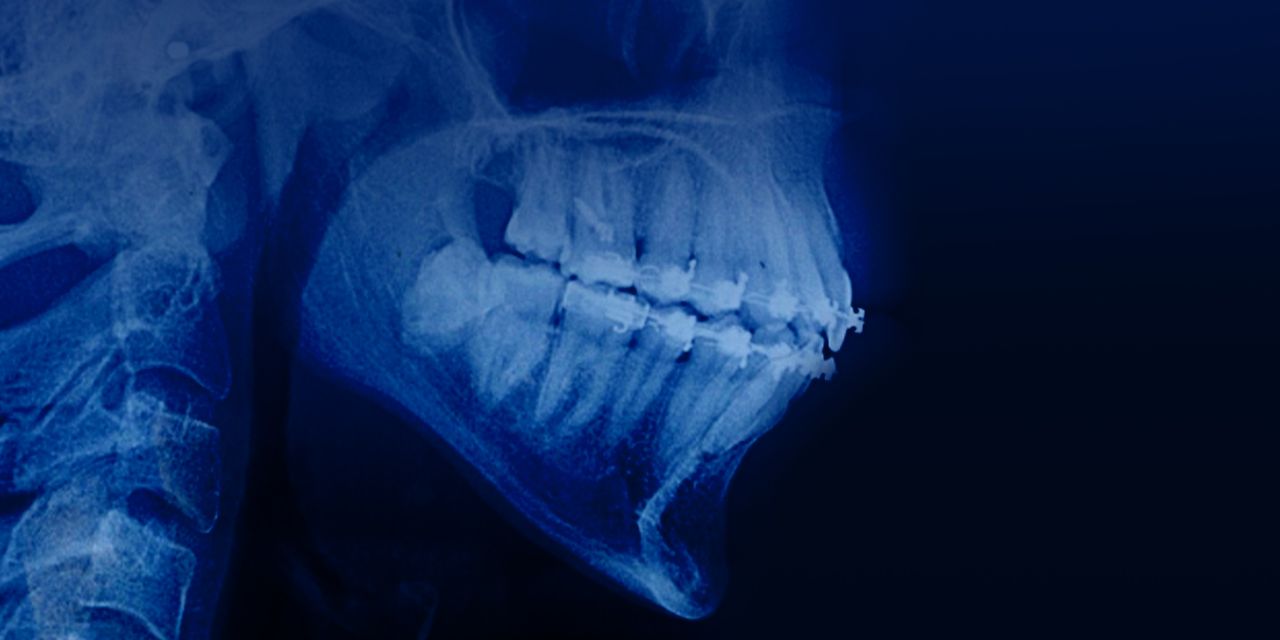

All I know about the treatment of adult patients with aligners

– Fixed vs aligners: comparison of aesthetics and efficiency

– Invisalign® treatment protocol

– Disadvantages of using fixed appliances

– Complications in the treatment of aligners

– 10 aspects for the use of aligners

– Treatment of age-related patients with Invisalign®: indications

– Difficulties in the treatment of patients with periodontal diseases

– Protocol of treatment of class 2 and class 3 malocclusion with aligners.